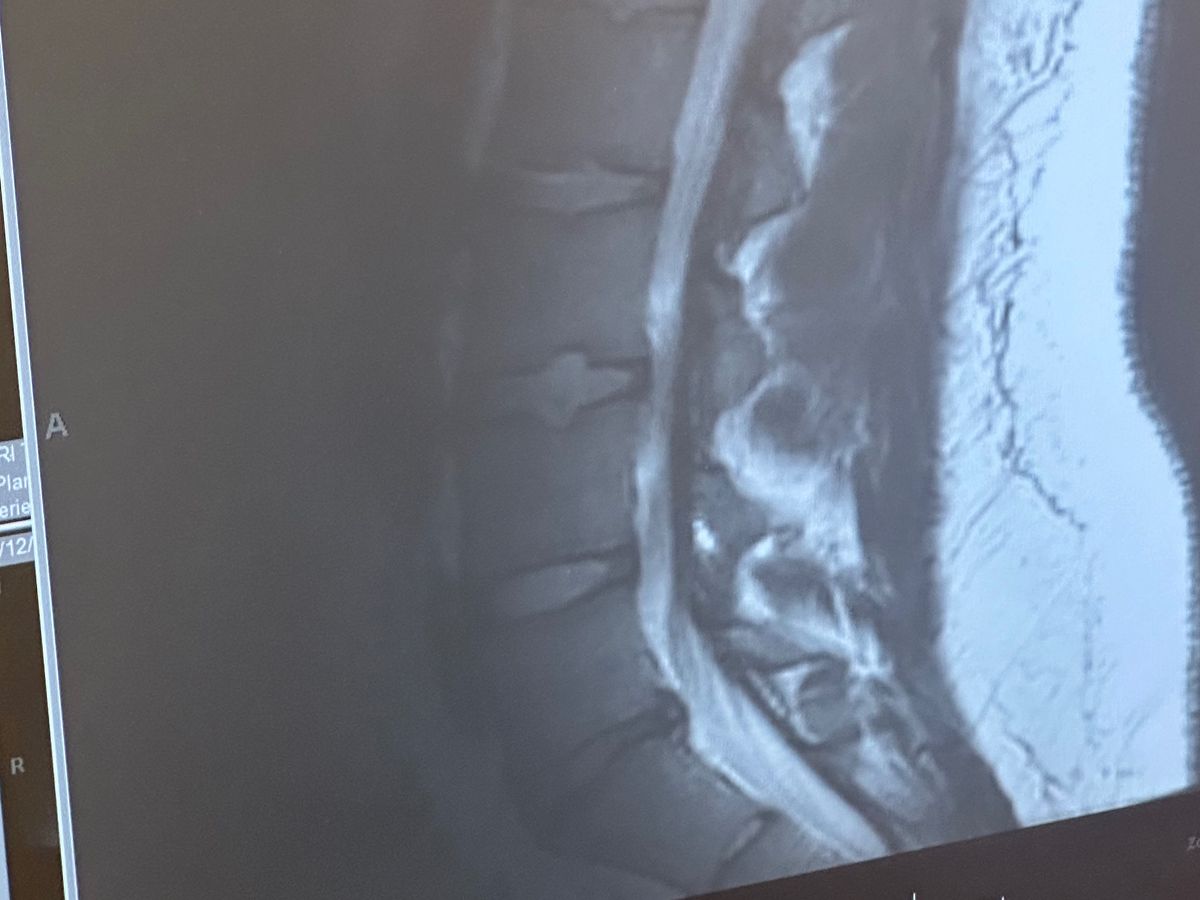

On Mother’s Day, I landed myself in the ER due to a flare-up of pain worse than I can recall. The ER determined the herniated disc has worsened, causing sciatica and damaging the nerves in my leg which has led to me losing a majority of feeling in my right leg and being unable to walk without a cane. After working with several doctors and getting lots of MRIs and tests done, the determination was made that the next course of action is surgical. This surgery should stop the rapidly increasing severity of pain and numbness in my back and legs and hopefully prevent the loss of sensation and feeling from becoming permanent.